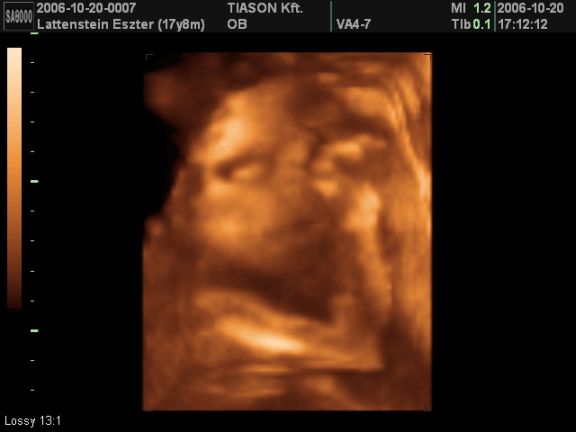

még ez lett a legjobb kép róla:)